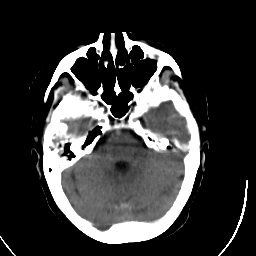

Stroke CT #3 -- Slice #6

[Home][Help][Clinical] Slice 6